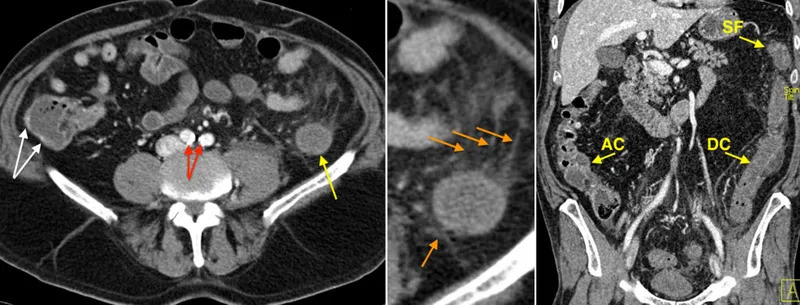

- Ischemic Colitis (IC)

- Most common mesenteric ischemia; typically non-occlusive (low flow).

- Key sites: Watershed areas (splenic flexure, rectosigmoid junction).

- Clinical: Sudden cramping LLQ pain, hematochezia, tenesmus.

- Imaging: "Thumbprinting" (submucosal edema/hemorrhage) on CT/barium.

⭐ Ischemic colitis most commonly affects watershed areas like the splenic flexure and rectosigmoid junction.